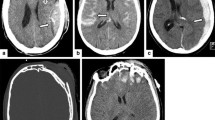

A thorough search should be undertaken to identify all entry points, which are usually smaller than the exit wound [10]. When a fragment passes through the bone, identifying the direction of injury is easier as it will cause beveling in the direction of travel (Fig. 7b), meaning that the entry site is sharp edged, while the exit side shows large inward-sloped bevel [18]. It is important to use a wide window level (soft tissue or lung window) to identify interruptions of the skin and soft tissues (Fig. 4b), findings that may point to the entry site. In many cases, the entry area will be obvious due to the significant disturbance of the tissue, but the exact entry point needed to perform accurate reconstructions of the shrapnel trajectory will be difficult to locate.

When no fragment is identified throughout the body, a search for exit wound should be performed. The exit wound is usually larger than the entry wound and show everted edges [22]. The typical outward beveling of the bone can be seen at the skull wounds [23]. Similar findings can be seen at times in the soft tissues. Furthermore, when there is a shower of fragments in the same direction, one can assume a common path to all of them, and then there is no need to track each separately.